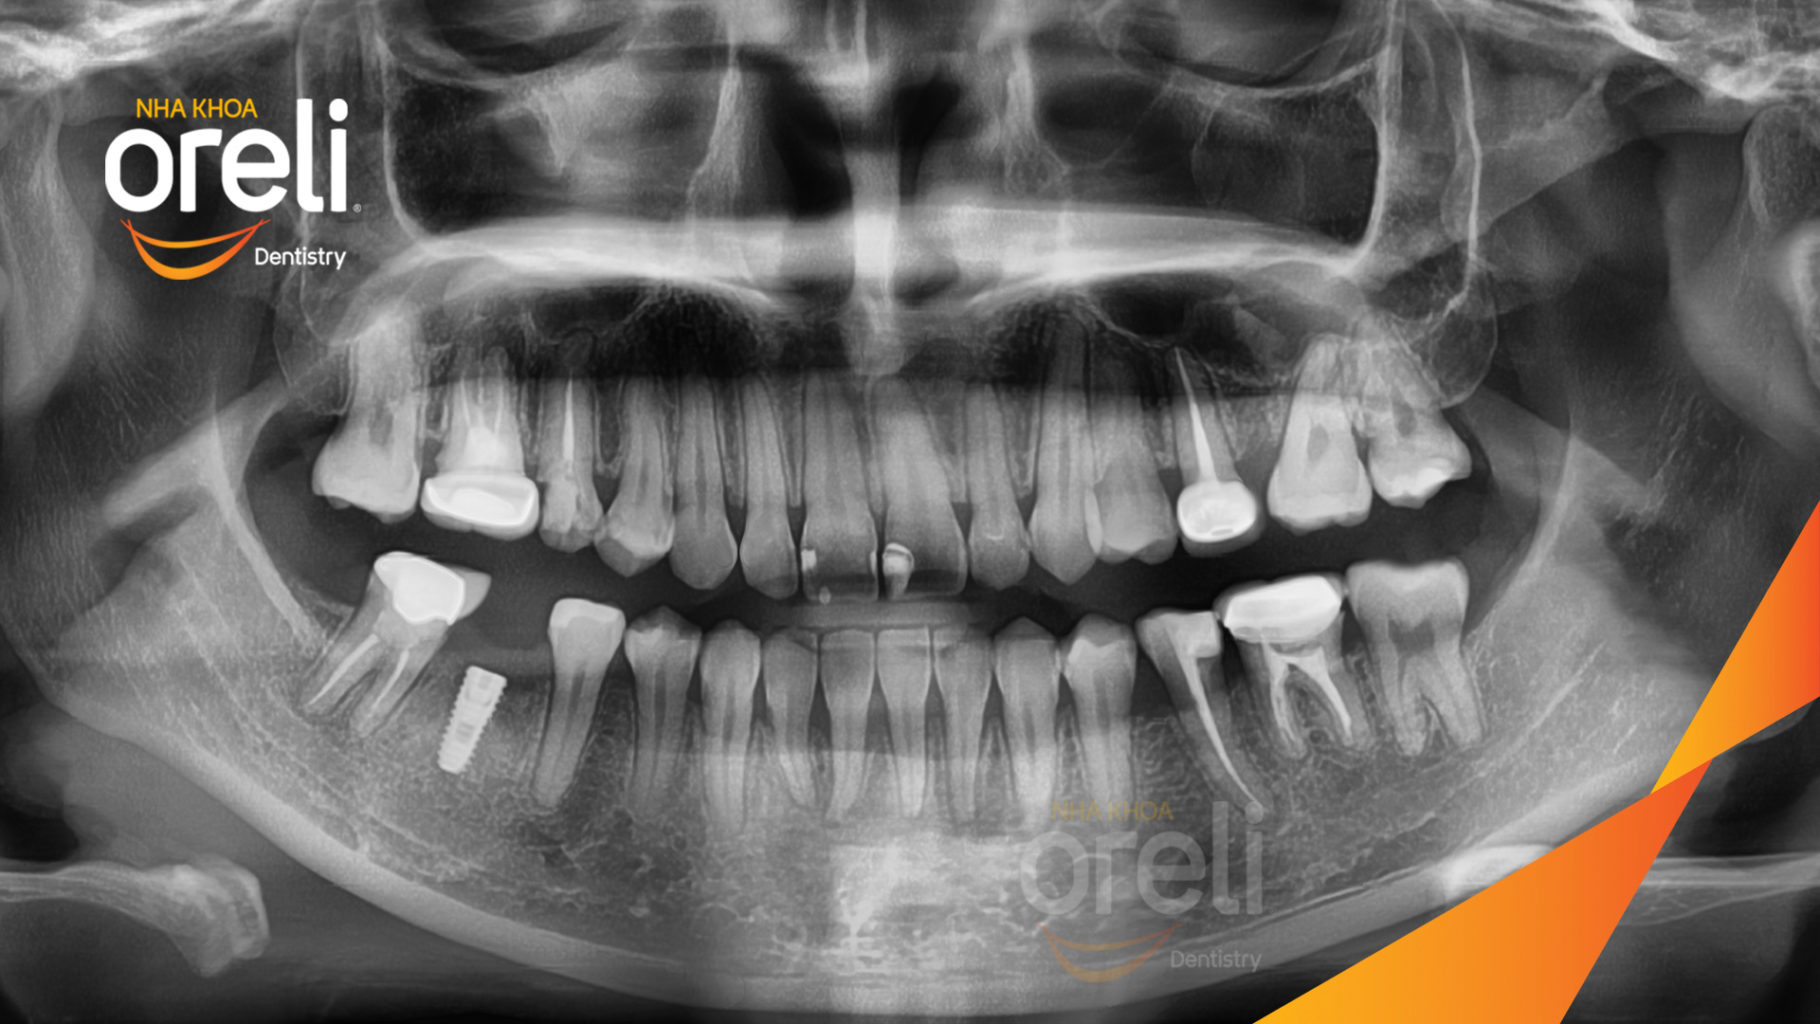

Ca niềng hạng 3 móm di gần răng 78 cho nụ cười đẹp ở Oreli

Ca niềng răng di gần răng 7 8 phục hồi ăn nhai và thẩm mỹ nụ cười. Kết quả thực tế trước và sau điều trị tại Nha khoa Oreli.